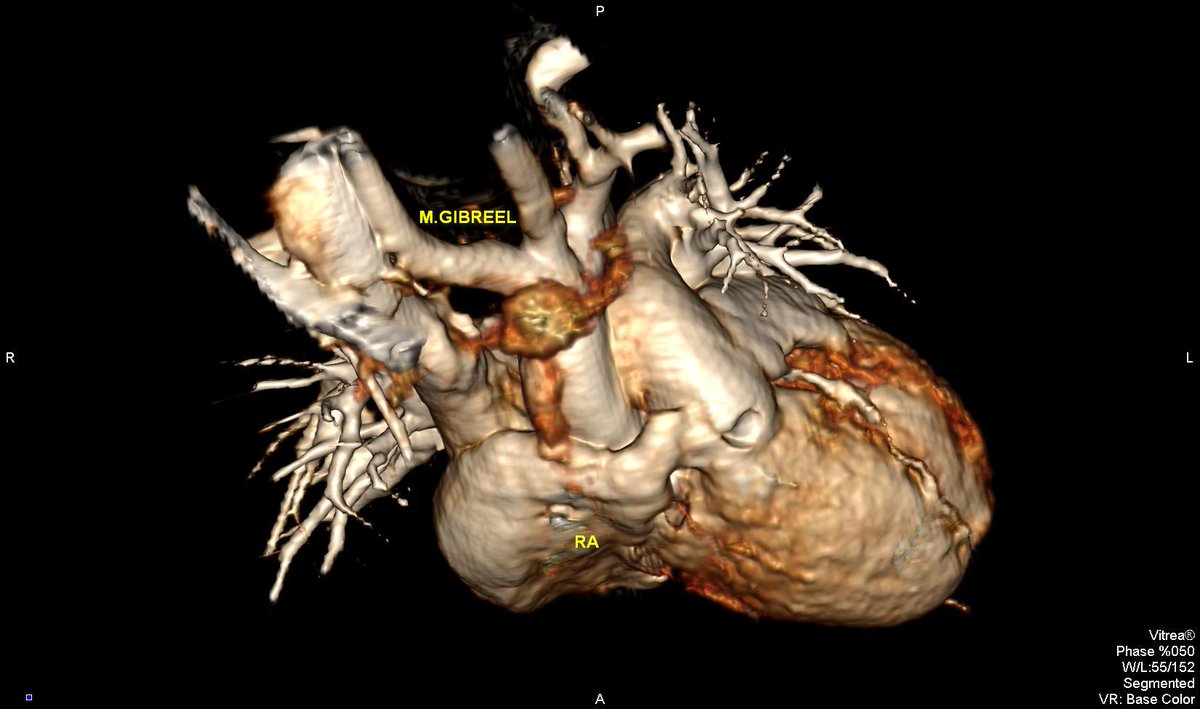

Subsequent chamber deformation : Two patients,,, RV & RA geometric deformation in pectus excavatum,,, From my archive

MGibreel1's tweet image. Subsequent chamber deformation :

Two patients,,,

RV & RA geometric deformation in pectus excavatum,,,

From my archive